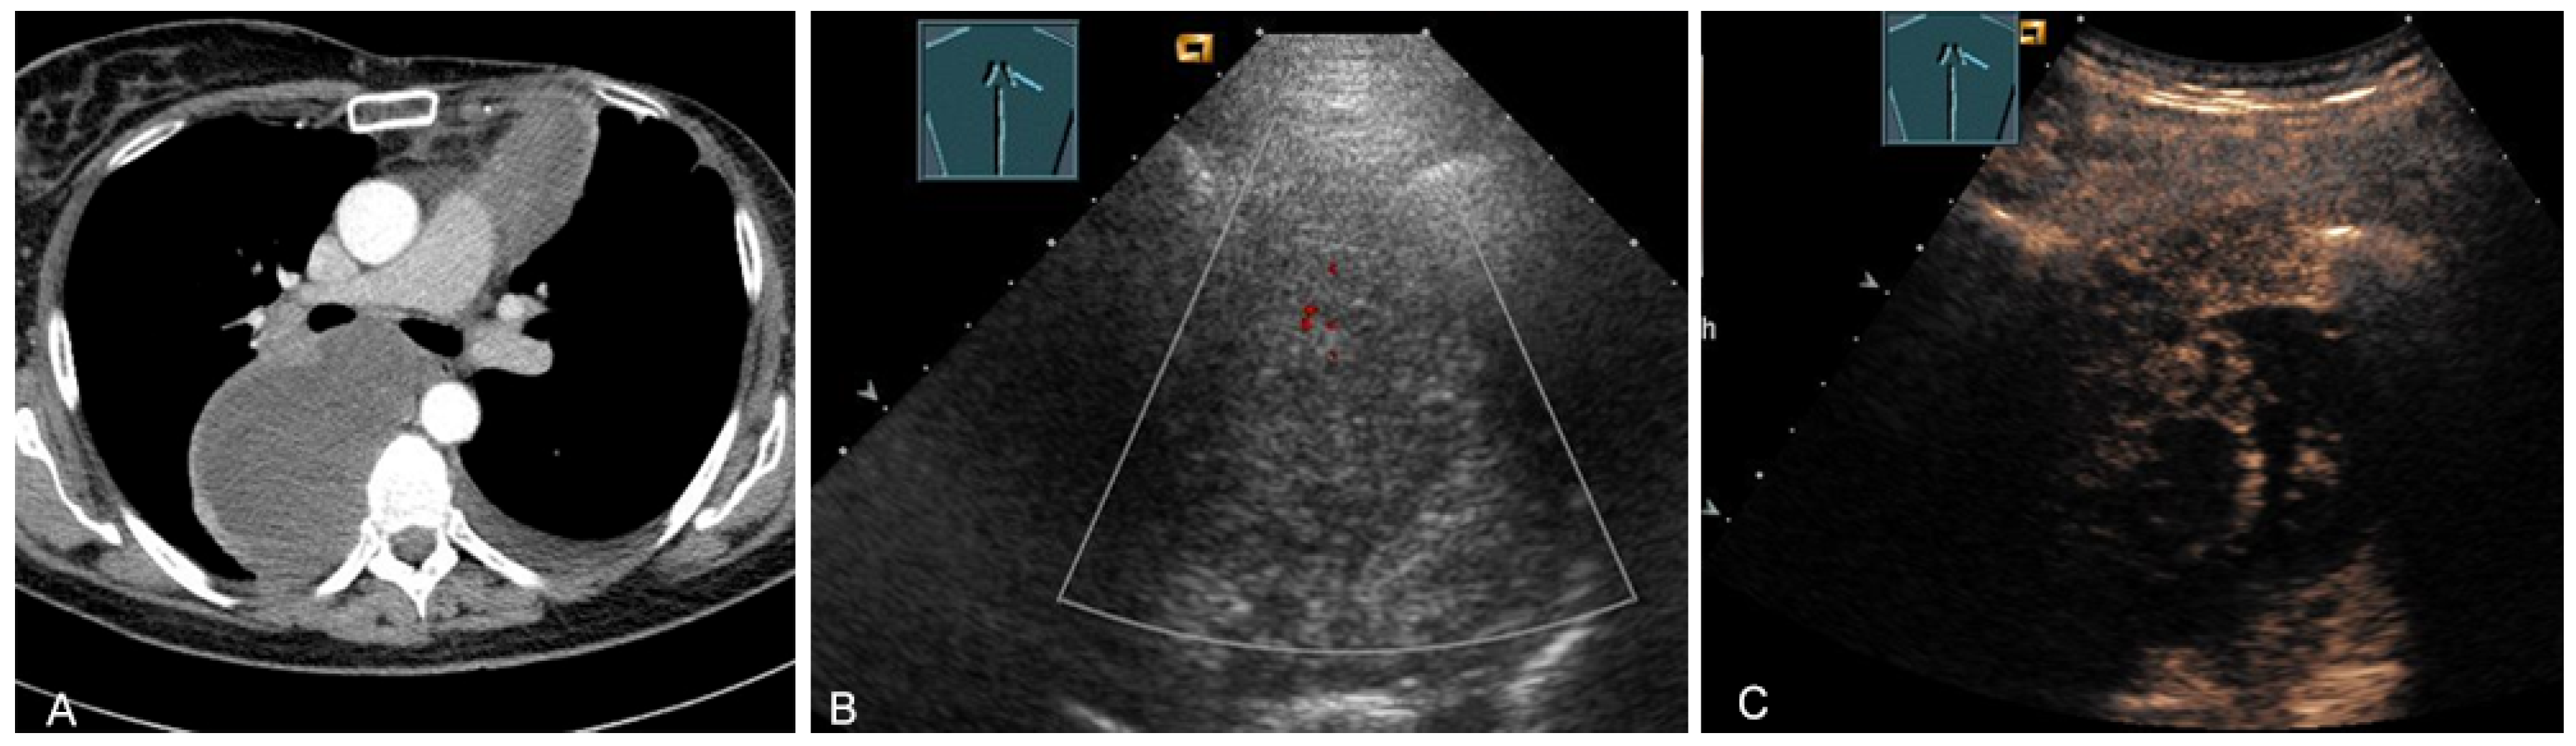

Enlarged lymph node metastases can be visualized on TUS if they are located in the prevascular superior mediastinum (Figure 26 and Figure 27) and inferior jugular region [28].

Figure 26.

A patient with tumor formation in the anterior mediastinum on CT (A), B-mode US (B), and CEUS (C), with anamnestic osteosarcoma, confirmed by biopsy as mediastinal metastasis.

Figure 27.

A patient with tumor formation in the anterior and paravertebral mediastinum on CT (provided by Prof. Dr. Andreas H. Mahnken, Marburg, Germany) (A), B-mode US (B), and CEUS (C), with anamnestic phyllodes tumor of the breast, confirmed by biopsy as mediastinal metastasis.